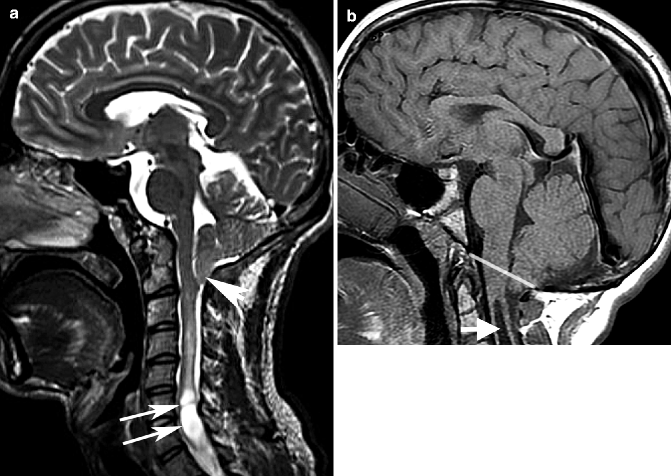

Examples Of Chiari Malformation Cm Subtypes A Upper Cm Type 1 Download Scientific Diagram